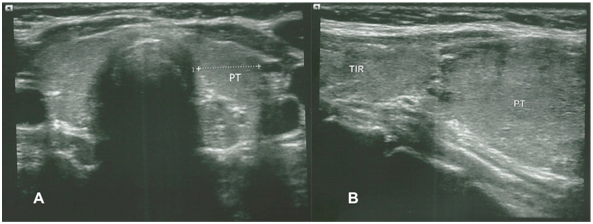

Based on these clinical, radiographic and laboratory results, the diagnosis of acute pancreatitis was made and the etiology of hypercalcemia was suspected. Further evaluation confirmed the primary hyperparathyroidism diagnosis, with elevated parathyroid hormone levels (iPTH: 462pg/ml, normal range 10-65pg/ml). Ultrasound and Tc-99m-sestamibi SPECT (single-photon emission computed tomography) scan examination demonstrated a solitary mass below the left lobe of the thyroid gland, compatible with lower parathyroid (Figure 1) (Figure 2). A head and neck computed tomography (CT scan) was performed; it showed an enlargement of the left thyroid lobule, but it was not clear if there was a parathyroid tumor (Figure 3). When the abdominal symptoms were completely controlled, the patient underwent surgical neck exploration finding a small left thyroid with a large brown polar nodule, which was sent for frozen section. Analysis confirmed an enlarge parathyroid gland adjacent to the left thyroid lobule, with local invasion of surrounding tissues (Figure 4). The decrease in serum calcium levels and normalization parathyroid hormone levels were confirmed postoperatively. At three and sevenmonths following surgery, the iPTH level was 34pg/ml, then 26pg/ml; calcium level was 8,7mg/dl, then 8,8mg/dl; phosphorus was 3,27mg/dl, then 3,32mg/dl, respectively.

Figure 1 Ultrasound of neck: Showed upper left 8mm thyroid nodule (TIR), and lower left 30mm parathyroid (PT).